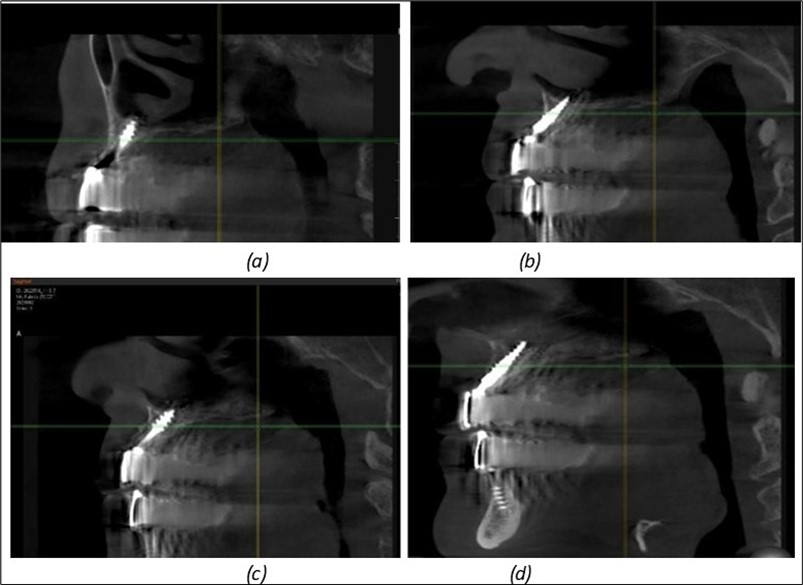

Figure 8.(a), (b) Sinus lift and grafting area with two stage implants before their removal. (c) area of fixation of BCS and TPG implants, avoiding the sinus lift and grafting area

Figure 9.Implants in the pterygoid plateau area: (a) TPG implant fixed in the maxillary-sphenoid junction area, quadrant 1; (b) TPG implant fixed in the maxillary-sphenoid junction area, quadrant 2.

Figure 10.Implants in the palatal sinus cortical area to avoid bone grafting: (a) BCS implant partially fixed in the graft material mass, partially in the palatal cortex; (b) Implant fixed in the palatal cortex at the junction with the nasal cortex, behind the graft material mass.

Figure 11.Implants in the anterior area anchored in the nasal cortex (BCS and TPG): (a), (c) – BCS implants fixed in the nasal cortex; (b), (d) – TPG implants fixed in the second nasal cortex with compression in the trabecular area.